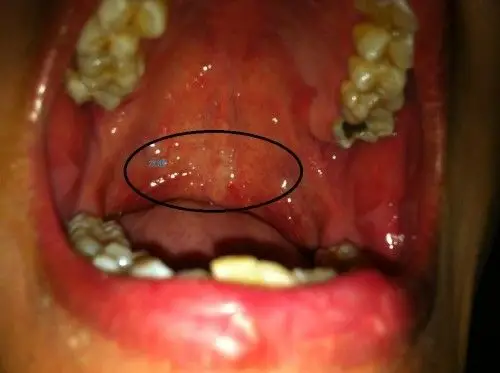

咽喉有水泡症状图片

探索 咽喉有水泡症状图片 相关的精美图片,激发您的创意灵感,为您的项目增添独特的视觉效果。